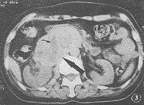

图3 恶性非功能性副节瘤 CT平扫示肾前区肿瘤(大箭头)压迫侵犯右肾,肿瘤内部囊变呈低密度区(小箭头)

2.3 病变大小:病变最大径<5 cm者6例(图1,2,5,6),其中良性5例,恶性1例;功能性5例,非功能性1例。病变5~10 cm者5例(图3),其中良性4例,恶性1例;功能性1例,非功能性4例。病变>10 cm者3例(图4),均为恶性;功能性1例,非功能性2例。

2.4 病变形态:病变边缘呈光滑圆形结节状3例,均为良性(图1,2,6),有不同程度分叶切迹,或呈分叶不规则状11例(图3,4,5)。

2.7 病变质地:病变密度或信号强度呈均匀者7例(图1,5),不均匀者2例(图2),有明显坏死囊变者5例(图3,4),其中1例有小点钙化。伴有坏死囊变者5例中4例为恶性,1例为良性。